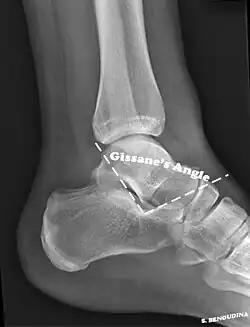

Gissane's angle

The Angle of Gissane, or "Critical Angle", is the angle formed by the downward and upward slopes of the calcaneal superior surface. On a lateral radiograph, an angle of Gissane > 130° suggests fracture of the posterior subtalar joint surface. Böhler's angle, or the "Tuber Angle", is another normal anatomic landmark seen in lateral radiographs. It is formed by the intersection of 1) a line from the highest point of the posterior articular facet to the highest point of the posterior tuberosity, and 2) a line from the former to the highest point on the anterior articular facet. Böhler's angle is normally 25° to 40°.[14] It is named after Austrian physician Lorenz Böhler.[16] A decreased angle is indicative of a calcaneal fracture.